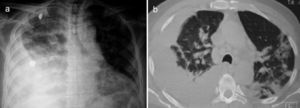

Un varón de 67 años de edad fue hospitalizado por disnea y fiebre de una semana de evolución. A su ingreso, el paciente se encontraba en malas condiciones generales y con una SatO2 del 78% respirando al medio ambiente. Sus signos vitales fueron FR 29min, FC 112min, TA 145/85mmHg y una temperatura de 37°C. La exploración física reveló un síndrome de derrame pleural derecho y muy escasos estertores finos en el hemitórax izquierdo. La radiografía de tórax y tomografía computarizada demostraron opacidades alveolares bilaterales y corroboraron la presencia de un derrame pleural derecho (fig. 1). Por laboratorio solo se documentó una leucocitosis de 21.400células/μl, de las cuales 9.400células/μl correspondieron a linfocitos. No presentó elevación de azoados y el examen general de orina no evidenció sedimento ni proteinuria. En la toracocentesis, un líquido amarillo turbio se obtuvo con un pH7,0; proteínas 6g/dl; glucosa 22mg/dl; DHL 1,066U/l, escasos polimorfonucleares y sin presencia de bacterias en la tinción de Gram. El paciente fue tratado inicialmente como neumonía asociada a un derrame pleural complicado y un tubo pleural le fue insertado en el hemitórax derecho al tiempo que le fue iniciado moxifloxacino 400mg IV cada 24h y meropenem 1g IV cada 8h, posteriormente, dicho esquema fue sustituido por vancomicina 500mg IV cada 6h y piperacilina 4g/tazobactam 0,5 g IV cada 6h. Sin embargo, durante los siguientes días no se observó mejoría clínica ni radiológica, y el drenaje de líquido pleural persistió a pesar de dichos esquemas antimicrobianos. La baciloscopia, los cultivos de líquido pleural y de sangre resultaron negativos. Tras una larga estancia en el hospital el paciente presentó una dermatosis generalizada (fig. 2a), y en una biopsia de piel se documentó una vasculitis linfocítica (fig. 2c). Este escenario se atribuyó inicialmente a un efecto adverso de los antimicrobianos. El panel de la hepatitis viral B y C, VIH, VDRL, pANCA y cANCA fueron todos negativos. Fue solo después de un examen físico detallado que se encontraron algunas úlceras en el pene (fig. 2b), sin embargo, la prueba de patergia no fue concluyente. El caso se diagnosticó como una forma incompleta de la enfermedad de Behçet versus granulomatosis de Wegener ANCA-negativa, por lo que fue tratado con metilprednisolona 125mg IV cada 6h presentando una rápida mejoría en sus condiciones generales y respiratorias permitiendo la retirada exitosa del tubo torácico y su alta hospitalaria al poco tiempo de iniciado el tratamiento. Desafortunadamente, el paciente falleció a las semanas siguientes debido a un cuadro de hemorragia alveolar difusa.

a) Pequeñas máculas rojizas y planas en los miembros inferiores producidas por vasculitis cutánea. b) Ulceración dolorosa en el pene. c) Microfotografía en la cual se observa una densa inflamación linfocítica alrededor de la pared de un pequeño vaso en un espécimen obtenido de la dermis (H&E, 400×).